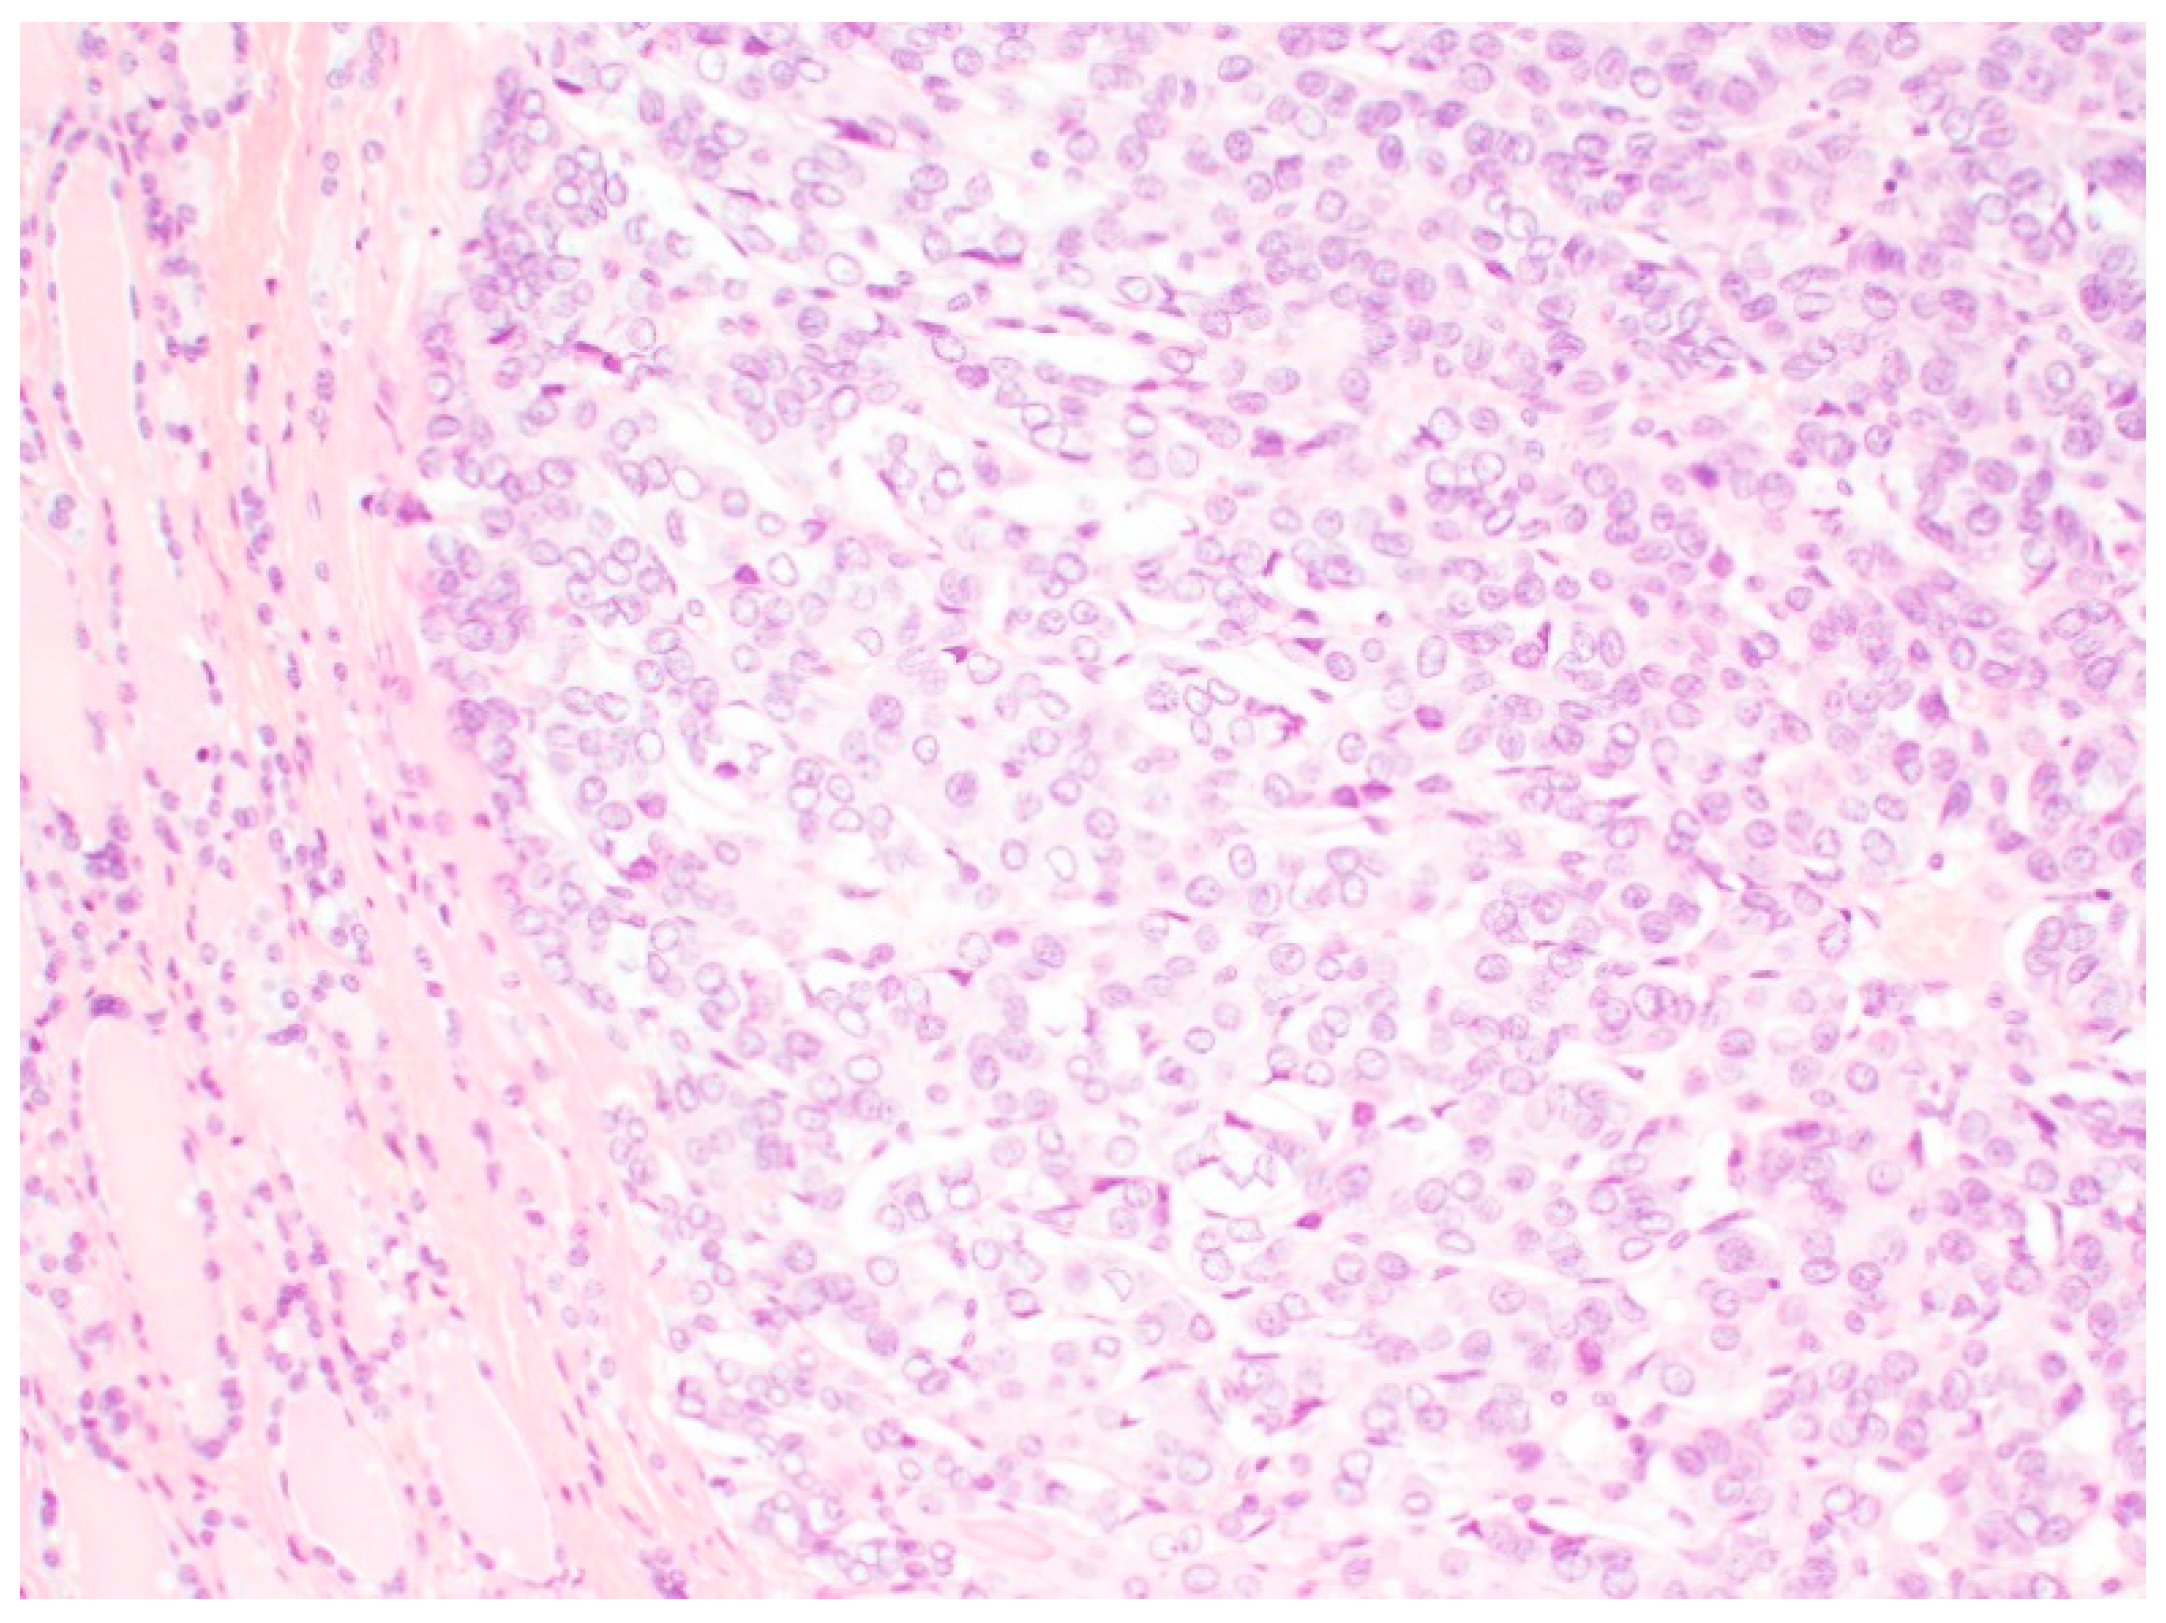

2. NIFTP: Histopathology